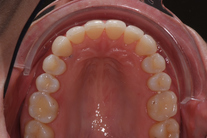

32-årig kvinna som tycker att hon bara visar sina framtänder. En utjämning och vidgning av tandbågen med 8 månaders genomskinliga Invisalignskenor, gav henne ett fint leende.